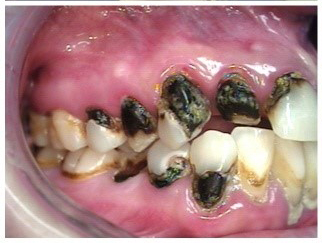

Often, the most visually striking manifestation of long-term meth use—known as “meth mouth”—is caused by the lack of saliva combined with an increase in soda drinking and extremely poor oral hygiene. This typically leads to meth abusers experiencing a large amount of caries. Decay begins with occlusal and facial caries and progresses rapidly, decaying to the bone level and often leaving only roots (Figure 1 through Figure 3).16

The patient in Figure 10 through Figure 12 was pregnant when she presented for dental treatment. The pregnancy was unplanned and she had had a lack of prenatal care. Continuing meth use during the pregnancy resulted in a positive toxic baby. She stated that she had just stopped using meth and had entered a rehabilitation facility a few days before. She was brought to the author’s clinic with a toothache. Note that as seen in these images, extreme accumulation of plaque, lack of oral hygiene, and severely decayed and missing teeth are classic manifestations in meth users.

Fig 10. Accumulation of soft plaque is typical of oral hygiene neglect associated with the use of methamphetamine.

Figure 10

Fig 11. Note demineralization of smooth surfaces, carious lesions at the gingival margins, and associated inflammation of the periodontium.

Figure 11